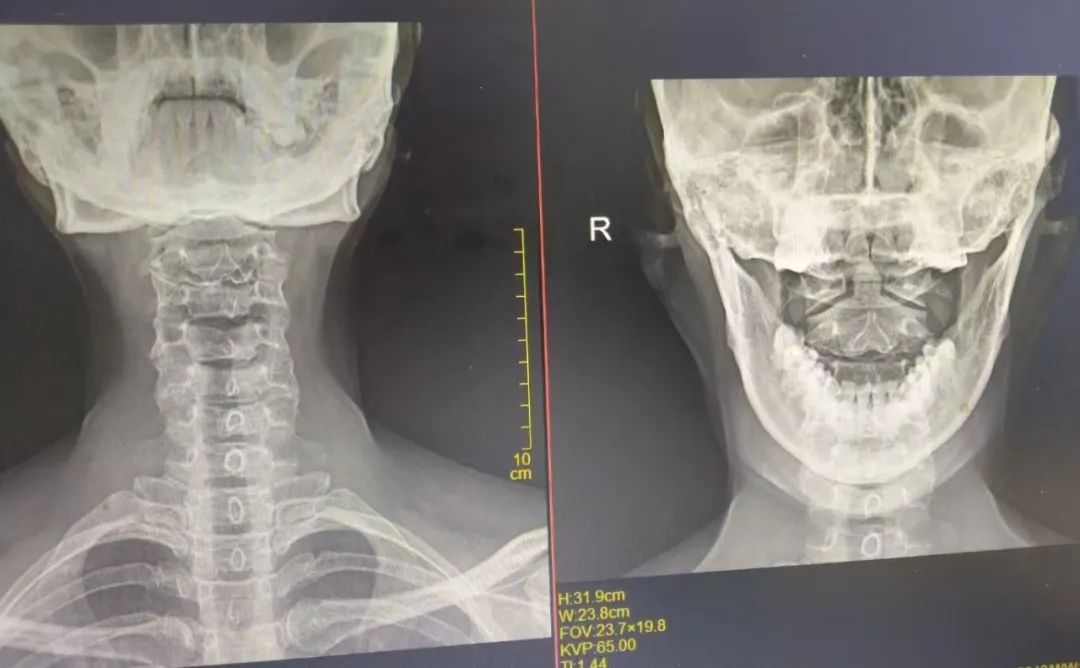

一次偶然机会,她来到了漳州第三医院中医科·康复科就诊。接诊的王承荣主任仔细聆听林女士诉说病情,在详细询问病史及查体后,医生发现一个关键细节:林女士除了长期受眼干、眼胀困扰以外,还伴随着头痛、颈部僵硬、肩背酸胀等症状,并且在长时间低头工作后,这些不适症状会进一步加重。凭借丰富的临床经验,王主任敏锐察觉到,林女士的眼部症状或许与颈椎病存在关联,随即建议她进行颈椎影像学检查。

检查结果印证了医生的判断,她的颈椎生理曲度变直,部分椎间盘向后突出,压迫神经根和椎动脉,导致颈部周围肌肉紧张,进而引发头部和眼部的牵涉痛。王主任解释道,颈椎病变刺激或压迫交感神经时,会引起眼部血管痉挛,减少泪液分泌,导致眼干、眼胀等类似干眼症的症状,同时还会引发头痛、头晕等不适。